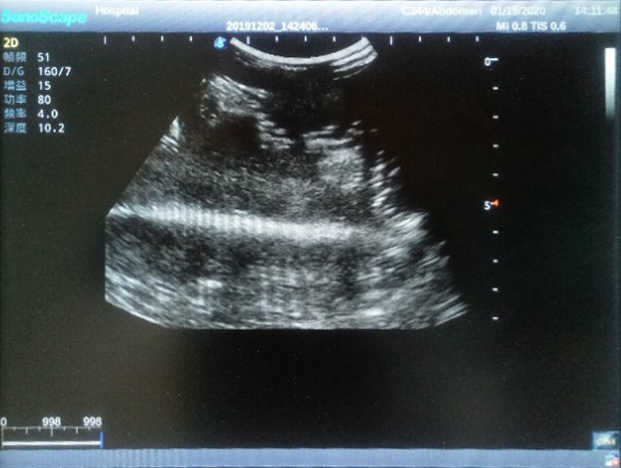

The Wearable Breast Ultrasound Examination Model allows users to develop and practice the skills necessary to gain proficiency in breast palpation, using ultrasound for normal and abnormal imaging and biopsy. It simulates adult female breasts with realistic size and appearance.

2)  Each model contains 8 space-occupying lesions of varying sizes, different in touch, elasticity and ultrasonogram

4) Biomimetic material allowing users to see clear and real normal tissues and space-occupying lesions that are hyperechoic, hypoechoic and isoechoic as they would see in the clinical environment